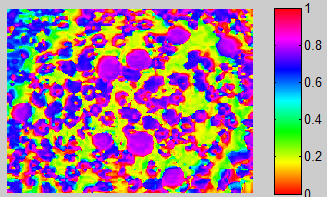

我要在一张包含另一种血细胞的图像中检测到白细胞,但是通过细胞的颜色可以分辨出差异,白细胞有更浓的紫色,可以在下面的图像中看到。

样本图像:

在这种特殊情况下,我会使用HSV。但与大多数颜色分割不同,我实际上会使用饱和通道来分割图像。细胞几乎相同的色调,所以使用色调通道将是非常困难的。

色调,(在完全饱和和完全亮度下)很难分化细胞